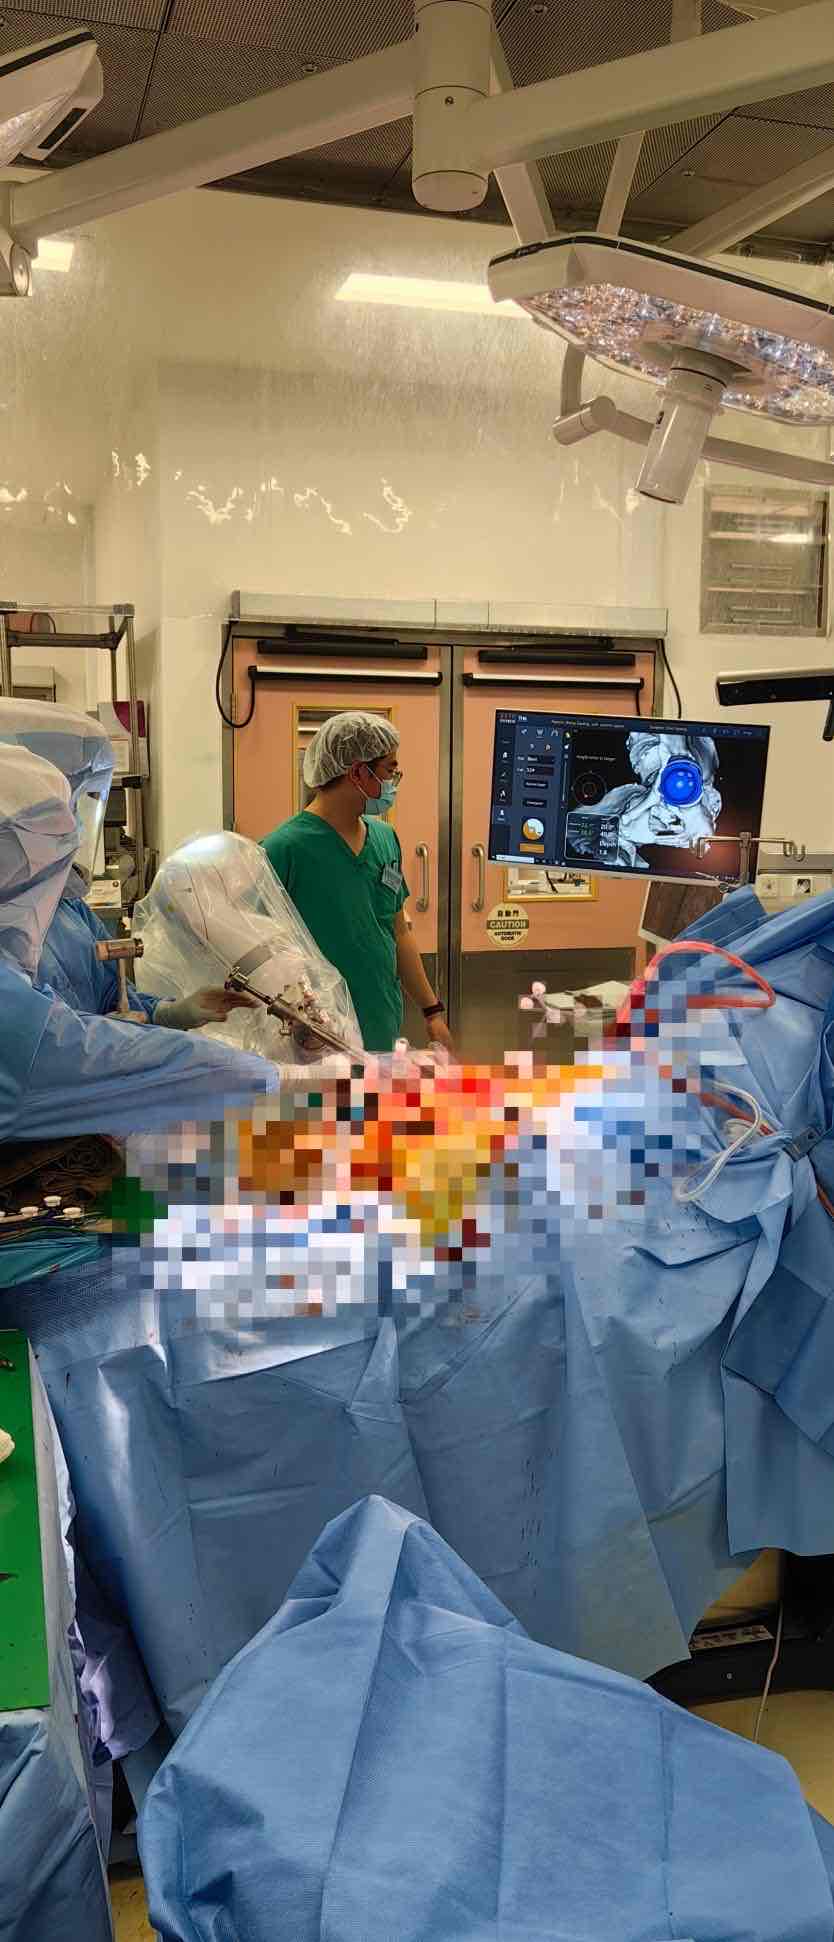

近日,香港雅丽氏何妙龄那达素医院骨科团队在蔡子龙医生主刀下,成功实施全球首例机器人辅助双拼Augment(Footing)髋臼修补全髋关节置换术。该手术依托元化智能自主研发的锟铻®全骨科手术机器人,针对一例合并严重髋臼上缘与外缘骨缺损的复杂病例,创新性提出“Footing假体”重建方案,标志着机器人辅助骨科手术在高难度关节重建领域实现重大突破。

在锟铻®机器人引导下,团队首先完成髋臼缺损区域的精准打磨,随后高效成型髋臼窝,并在导航探针实时指引下,将组合式“Footing假体”严丝合缝植入预定位置,最终稳妥置入髋臼杯。全程操作高度还原术前数字规划,真正实现“所见即所得、规划即手术”的精准医疗理念。

“这项手术的成功,是先进机器人技术与临床医生创新思维完美结合的典范,”蔡子龙医生术后表示,“若无锟铻®机器人提供的高精度模拟与术中导航,我们很难在术前就如此有信心地设计并实现‘Footing假体’这一方案。它让我们面对复杂重建手术时,拥有了前所未有的确定性与能力。”